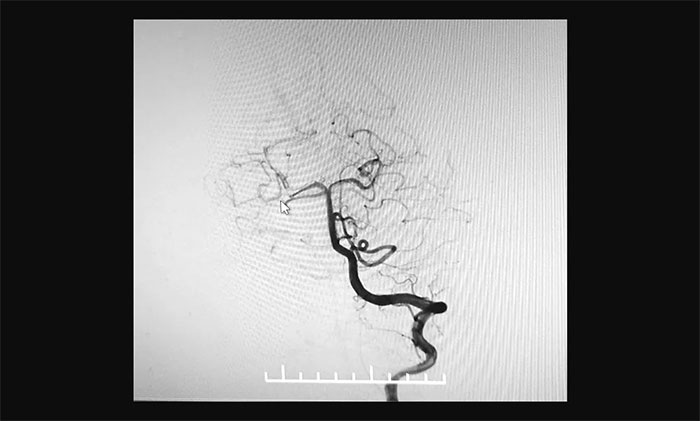

最终,在麻醉科团队及导管室介入团队的密切配合和监护下,神经外科于耀宇主任团队历时2小时,为王女士顺利实施脑血管造影+颅内动脉瘤栓塞术。术中,DSA造影确诊右侧小脑上动脉夹层动脉瘤,动脉瘤瘤体大小约为4x3 mm。术中,于耀宇主任凭借娴熟的技术,克服血管迂曲等困难,将栓塞导管成功送入夹层动脉瘤内,最终顺利栓塞夹层动脉瘤。术后,再次造影未见动脉瘤显影,见远端分支显影良好,“炸弹”危险被成功解除。术后,患者顺利苏醒,无神经功能障碍。

▲ 栓塞后